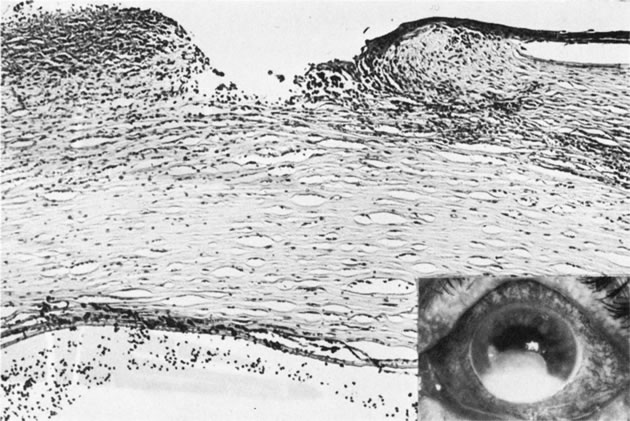

Syphilis is a venereal disease caused by the spirochete Treponema pallidum, which primarily affects the central nervous and cardiovascular systems. During the past decade, syphilis has again become more common. Often syphilis is found in patients who also have acquired immune deficiency syndrome (AIDS).101 The organism is highly infectious but of low virulence, resulting in long periods of latency and prolonged viability unless specifically treated. Many of the tissue effects of syphilis are due to host immune response, such as mononuclear cell infiltrates, proliferative vascular changes, and occasionally granuloma formation. The cornea often is not affected by acquired syphilis but is commonly affected by congenital syphilis (Fig. 12). Infection of the fetus occurs transplacentally after the fifth month of gestation. Diffuse fibrosis can compromise the function of any parenchymatous organ, including the lungs.

Fig. 12. Syphilis. A. Corneal ghost vessels as viewed by fundus reflex in a patient with congenital syphilis. B. Slit lamp appearance of interstitial keratitis. C. A blood vessel (arrow) present anterior to Descemet's membrane (d). D. Retrocorneal ridges of Descemet's membrane form refractile, branching straight lines. E. A multilayered strand extends from a thickened Descemet's membrane into the anterior chamber.(Courtesy of SEI Photoarchives.) (B Courtesy of Dr. W. C. Prayer; D and E from Waring GO, Font RL, Rodrigues MM et al: Alterations of Descemet's membrane in interstitial keratitis. Am J Ophthalmol 81:773, 1976.)

The cornea is particularly involved in a late-occurring form of congenital syphilis, which also causes periostitis, saber chins, saddle nose deformity, and tooth deformities (Hutchinson's teeth).102 Congenital syphilis presents between the ages of 5 and 10 years with an intense keratitis that may last for several months and may reduce visual acuity to counting fingers or seeing hand movements.103 Fortunately, usually a significant regression occurs with a parallel improvement of visual acuity, often in the range of 20/40 to 20/60. The acquired form of interstitial keratitis tends to be unilateral (it may even be sectorial) and tends to occur during the third or fourth decade of life as an expression of tertiary syphilis.

Histologically, the cornea shows edema and infiltration by lymphocytes and plasma cells. Vessels usually are seen in the deep portion of the cornea, just anterior to Descemet's membrane. Although the edema and inflammation of the corneal stroma resolves, the deep vessels persist in the form of ghost vessels. Often blood flow is minimal but persistent through the vessels, even though they appear empty. Chronic interstitial inflammation causes alterations of Descemet's membrane that are characteristic of congenital syphilis and include linear guttae with ridges and even nests of transparent basement membrane material, which may project into the anterior chamber.104,105